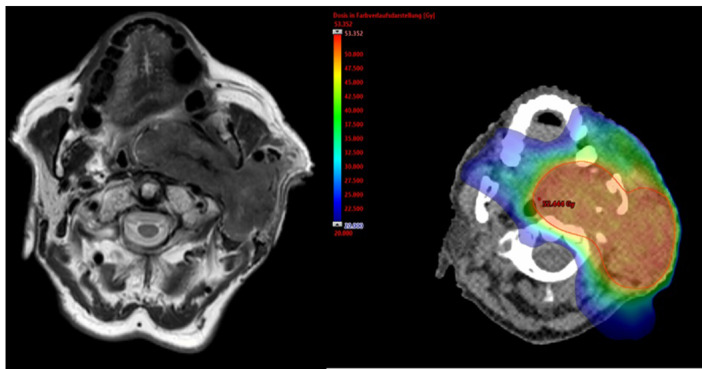

Radiotherapy Treatment of Warthin's Tumor (Cystadenolymphoma).

Warthin肿瘤(囊腺淋巴瘤)的放射治疗。